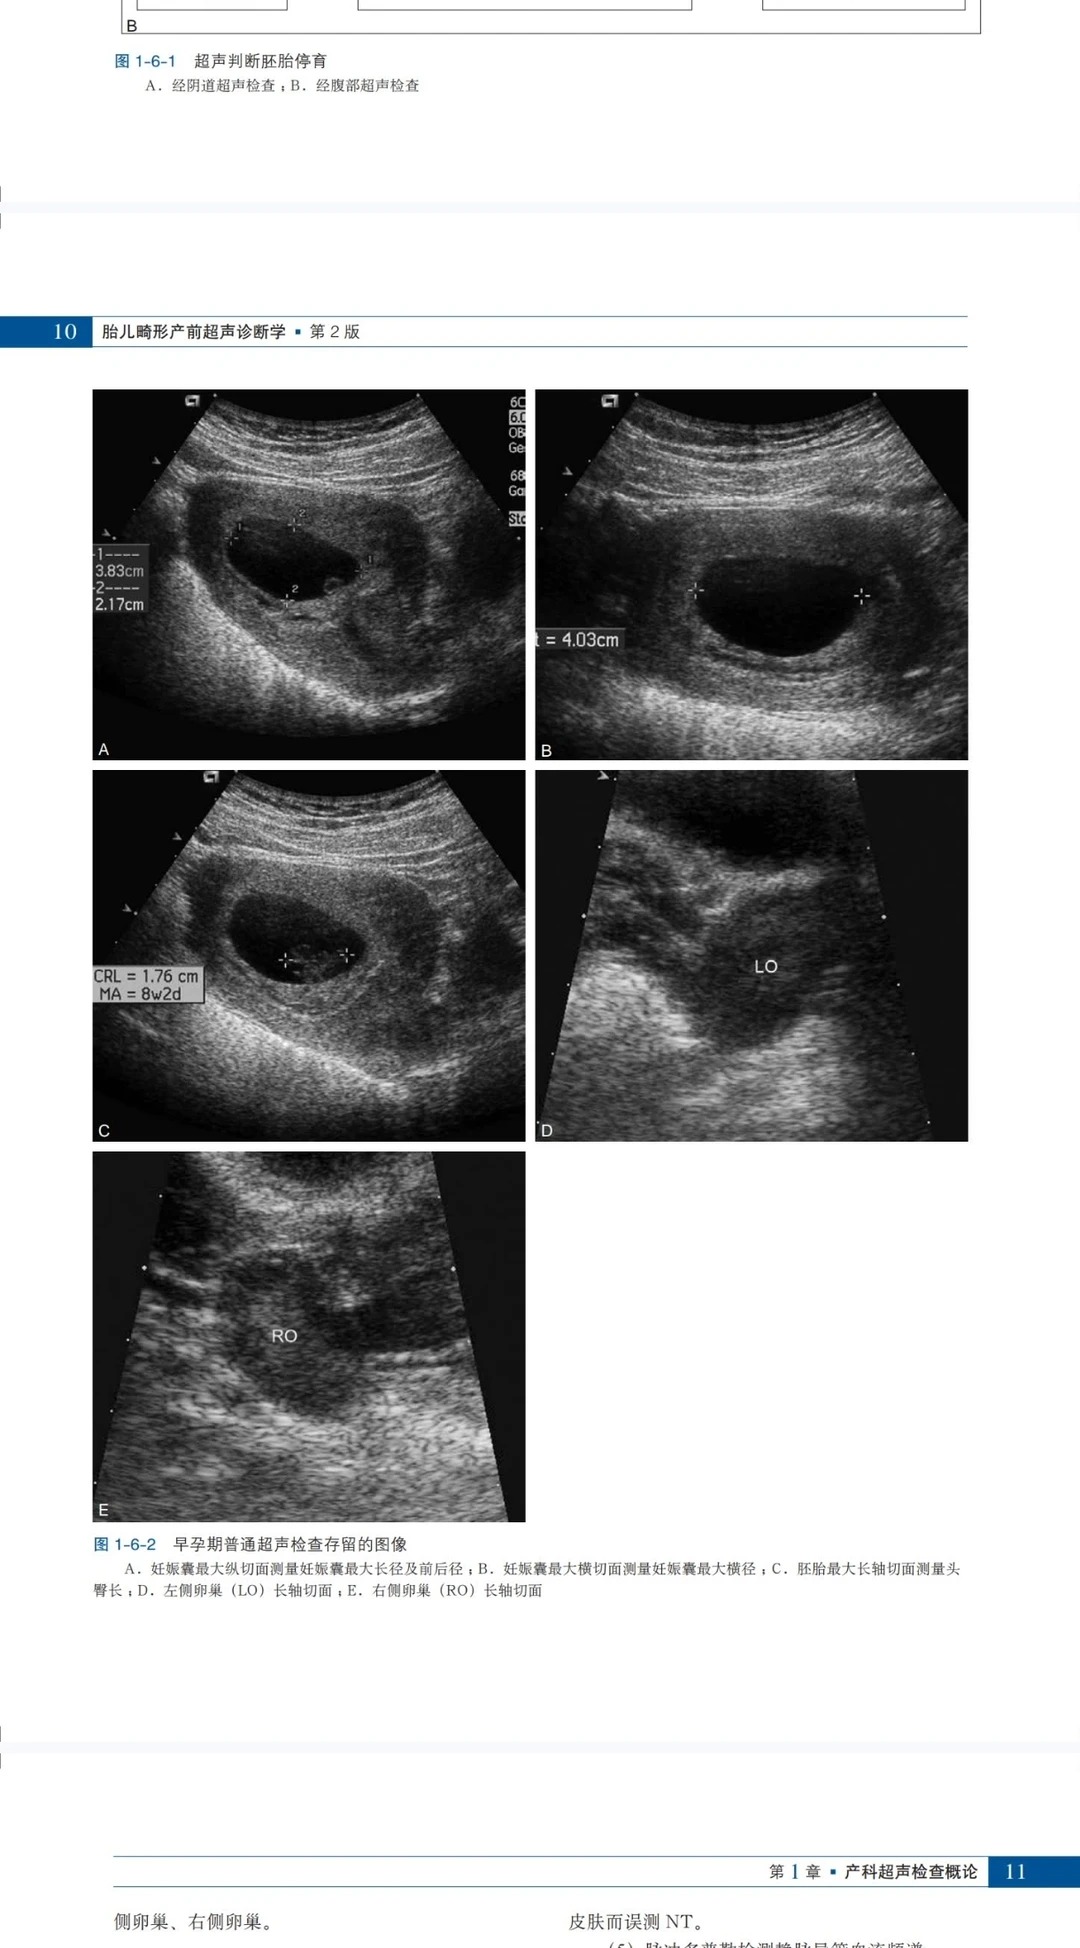

3. 图文直观,解读更轻松 附2000余幅高质量插图,涵盖模式图、产前及产后超声图、实体标本照片及X线片,图文对应、直观形象,清晰呈现胎儿畸形的形态特征和超声表现,帮助读者快速解读复杂超声图像,降低诊断难度,提升解读效率。